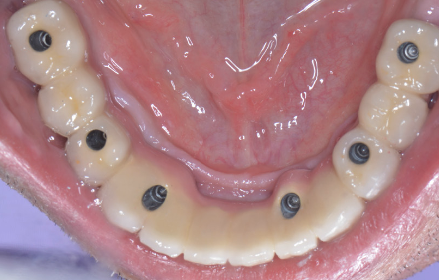

După acest interval lucrarea provizorie se îndepărtează, în fiecare implant se montează câte un dispozitiv necesar realizării amprentelor (Fig. 3.6.7) care vor servi tehnicianului dentar pentru realizarea punții definitive (Fig. 3.6.8 și Fig. 3.6.9). Realizarea acesteia se face în câteva zile, interval în care pacientul va continua să poarte lucrarea provizorie realizată inițial.

Lucrarea finală se va înșuruba pe componentele protetice ale implanturilor (Fig. 3.6.10 și 3.6.11), iar perforațiile de acces pentru șuruburi (Fig. 3.6.12) vor fi acoperite cu material compozit (Fig. 3.6.13). După fixarea definitivă (Fig. 3.6.14) puntea poate fi oricând detașată de către medicul dentist la nevoie, prin simpla îndepărtare a materialului compozit și desfiletarea șuruburilor de fixare.